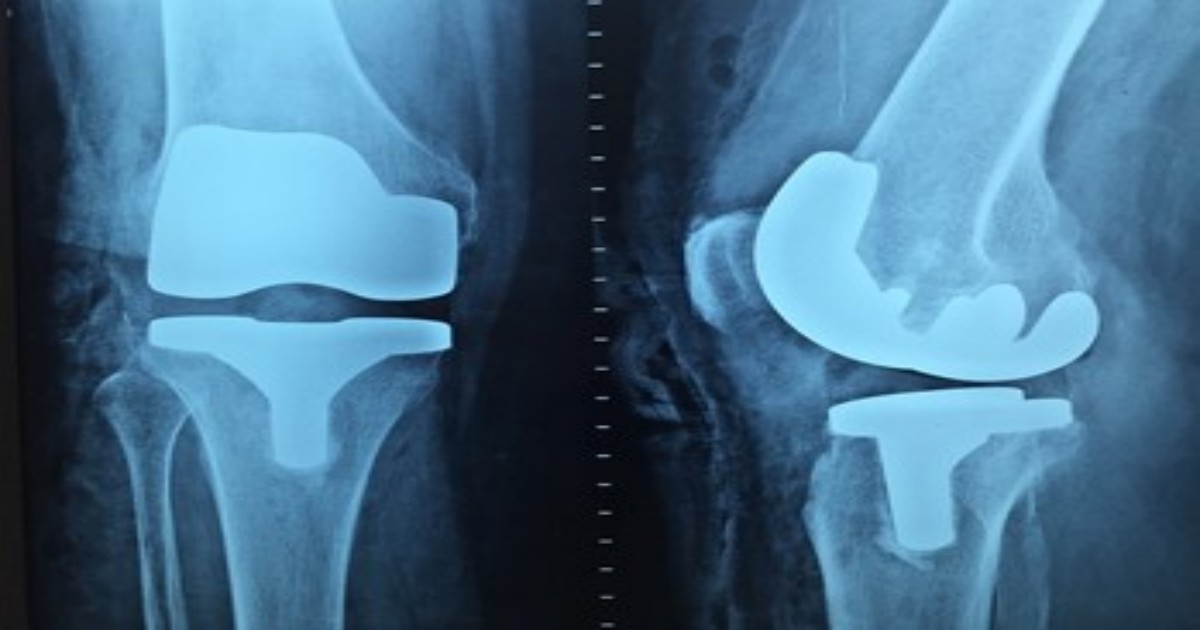

The Replacements section invites authors in the field of hip, knee, and ankle replacements. Since several interesting controversies still exist in the field of lower-limb joint arthroplasty, at least some of them should be addressed to yield approximate results.